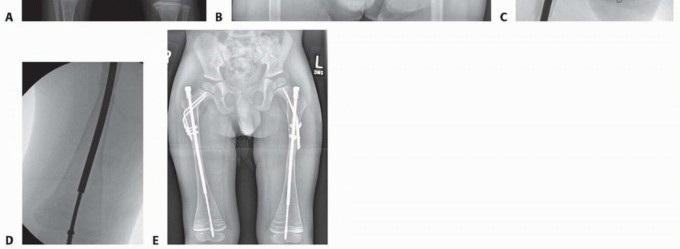

Tibial Technique

## Nails from the small bone set are used. These have a somewhat shorter female-threaded portion to avoid extension of the threads across the proximal tibial epiphysis.

## To perform the tibial osteotomy, a 1.5-cm incision is made. The periosteum is visualized and partially elevated. Multiple osteotomies may be necessary. However, in the vast majority of patients, a single incision with a segmental resection is preferable to multiple osteotomies (TECH FIG 6A).

## The key to the tibial osteotomy is to place the tibia in mild posterior bow to allow for anterior compression.

## Any residual anterior bow will lead to an increased risk of nonunion, progressive anterior bowing, and impede telescoping of the rod.

TECH FIG 6 • A. Incisions to correct tibial deformities. B,C. Note hole in male nail to allow locking with a wire if necessary. Correct placement of the distal male nail after complete correction of anterolateral bowing. D,E. Correct proximal tibial nail placement. F. Male nail cut in situ, which may require a more anterior entrance point, especially in smaller children, to accommodate the male nail cutter.

The guidewire is then passed beyond the osteotomy.

## Ideally, the entrance point to the distal tibial epiphysis is slightly posterior on the lateral view and slightly lateral on the AP view. This helps to avoid the tendency to valgus and anterior cutout.

## The male nail is either cut after determining the length with the C-arm before placement into the tibia or inserted, removed, and then cut after the appropriate length is determined (TECH FIG 6B-D).

## The female nail is cut to length in the same manner as for the femoral technique and inserted until the threaded portion is fully seated into the epiphysis.

## It usually is visible just a few millimeters deep to the articular cartilage, even when the C-arm suggests that the proximal nail is protruding into the joint (TECH FIG 6D,E).